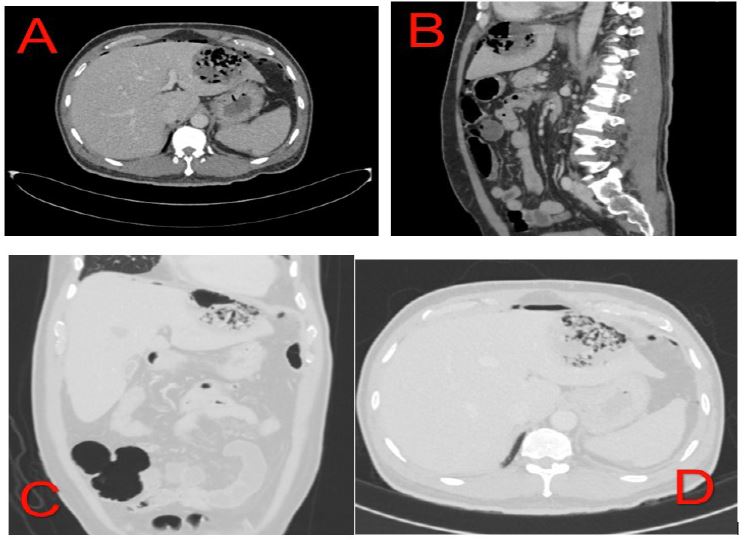

Initially the ER physician suspected it might be covid infection, hence CT and covid PCR was ordered for him. The test was negative for covid, and CT chest didn’t reveal chest infection, nevertheless, it showed air under diaphragm (Figure 1).

Figure 1: Showing air under diaphragm.